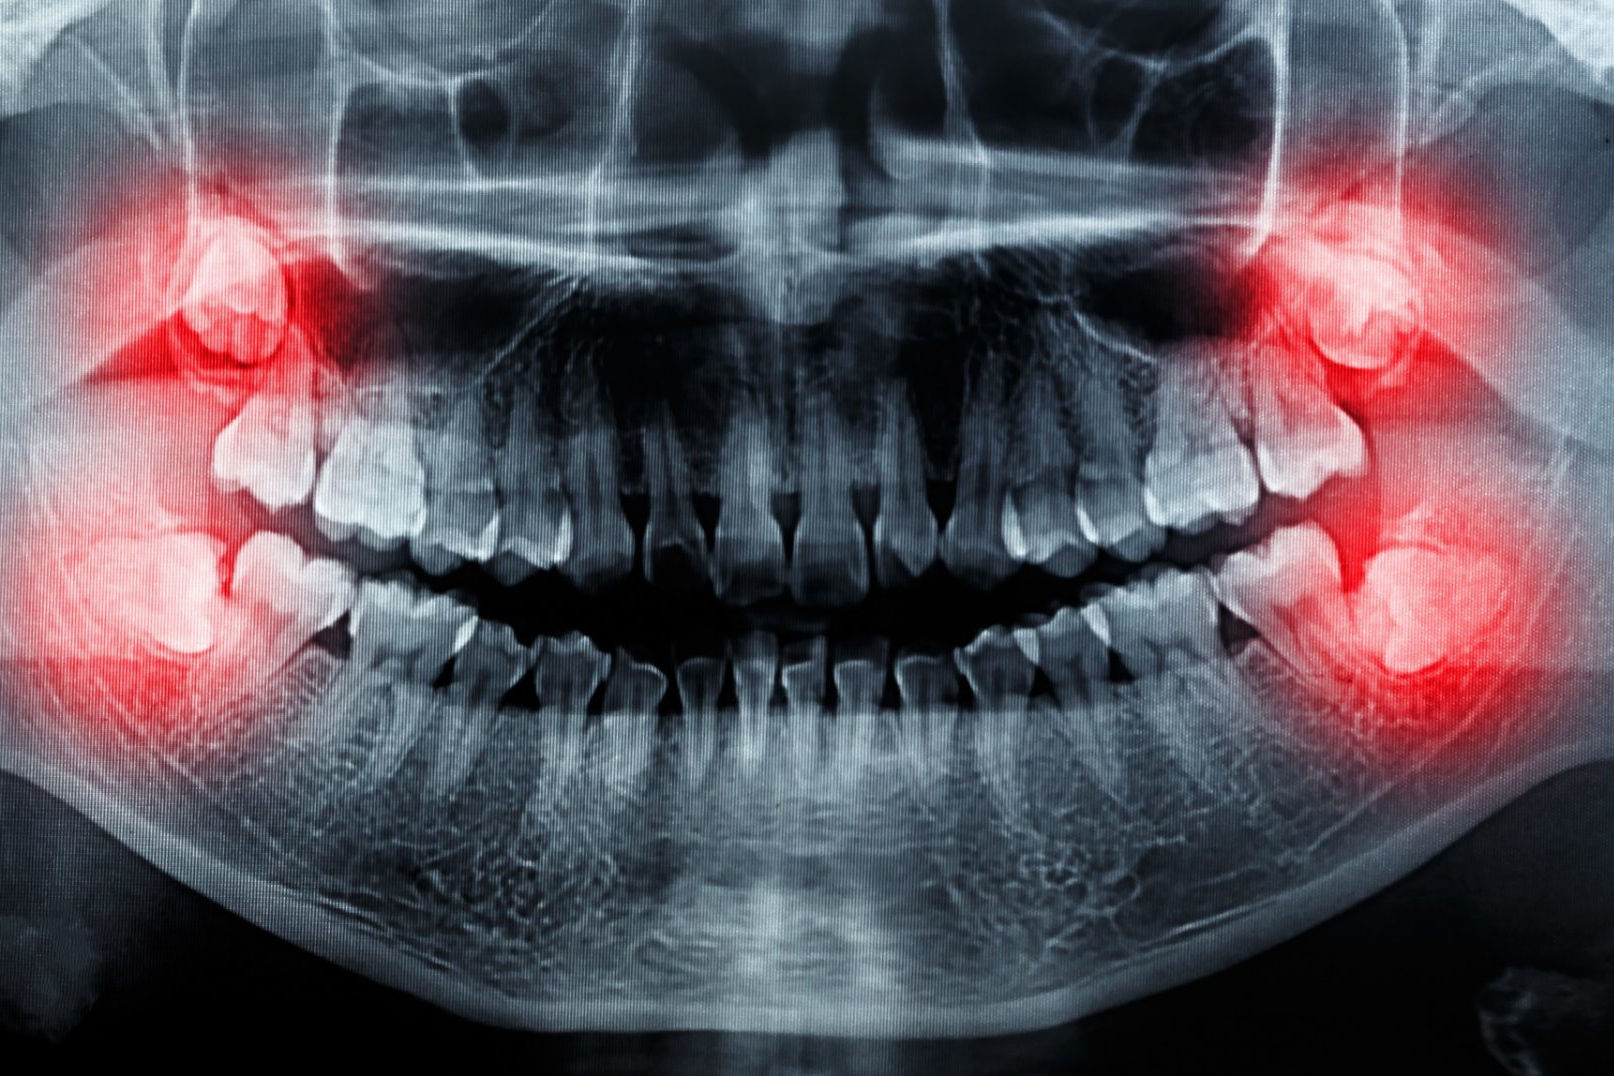

Chirurgische extraktionen – entfernung von Weisheitszähnen

Weisheitszähne sind in der Regel stark verankert, haben 3-4 Wurzeln und erfordern eine chirurgische Behandlung, um entfernt werden zu können. Weiterhin erleben wir oft, dass Weisheitszähne einwachsen, da sie auf verschiedene Weise im Kiefer stirnrunzeln können und ihre Position meist von der normalen abweicht. Dies lässt sich dadurch erklären, dass das Gesichtsskelett, insbesondere der Kiefer, im Laufe der Jahrtausende kleiner geworden ist und somit weniger Platz für die gleiche Anzahl von Zähnen zur Verfügung steht. Es kommt immer häufiger vor, dass sich die Weisheitszähne gar nicht bilden, so dass der glückliche Patient keine Probleme mit ihnen hat, da die Weisheitszähne durchkommen und den nötigen Platz haben.

Wenn ein Weisheitszahn nicht vollständig anwachsen kann und auf halber Strecke stehen bleibt, kann er sich entzünden. Auch die Reinigung dieser Zähne kann kompliziert sein, was zusätzlich für Entzündungen sorgen kann, auch unter dem Gaumen. Das kann Schmerzen, Karies und schlechten Mundgeruch verursachen.

Auch können sich Weisheitszähne in schlechter Lage negativ auf andere Zähne auswirken, zum Beispiel könnten sich die Zähne auf den Druck der Weisheitszähne nach innen bewegen, was zu Verzerrungen oder Stockung der anderen Zähne führen kann. In diesen Fällen muss dann oft eine Zahnsange für die Korrektur angewandt werden.